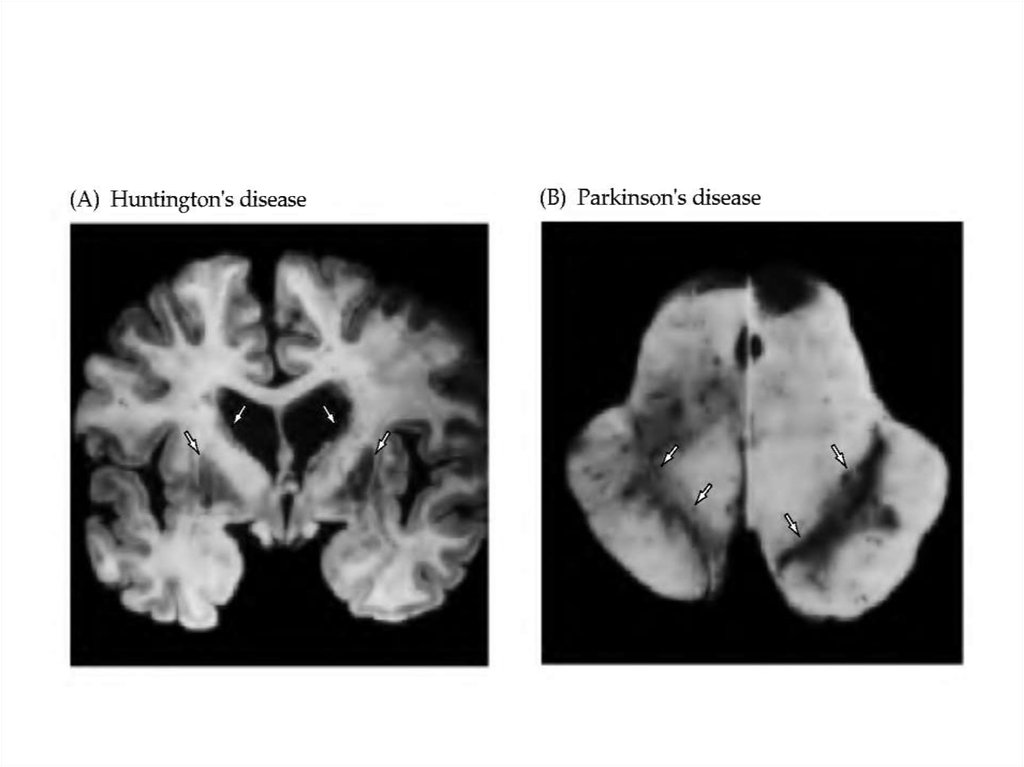

11. Паркинсонизм (болезнь Паркинсона)

Возникает при поражении дофаминергических нейронов

компактной части черной субстанции (снижение

концентрации стриарного дофамина), что приводит к

растормаживанию нейронов стриатума. Проявляется в виде

триады: мышечная ригидность - повышение тонуса мышц,

преимущественно сгибателей; акинезия (гипокинезия) снижение двигательной активности, обеднение движений,

их замедленность; тремор - дрожание различных

сегментов тела. При активных или пассивных движениях

тремор может исчезать. Иногда возникают вегетативные

расстройства. Характерны нарушения психики: снижение

инициативы, интереса к окружающему; эмоциональные

расстройства - эмоциональная тупость, раздражительность,

эгоцентризм, назойливость, импульсивность; снижение

интеллекта, деменция

12. Большая хорея (хорея Гентингтона)

Хроническое дегенеративное заболевание. Возникает при

поражении внутристриарных нейронов, при гибели

внутристриарных холинергических волокон и ГАМКергических волокон, идущих от стриарных нейронов к

нейронам черного вещества. Кроме того, наблюдается

повышение функциональной активности

дофаминергических нейронов черного вещества,

проецирующихся в стриатум. Проявляется гиперкинезами

(непроизвольные размашистые движения конечностей,

больные гримасничают, при ходьбе раскачиваются,

пританцовывают и т.д.), нарушениями речи (медленная,

неравномерная). Возникают психические расстройства

(эмоциональные нарушения, нарушения памяти, снижение

интеллекта, деменция) и галюцинаторные психозы. Течение

- прогрессирующее